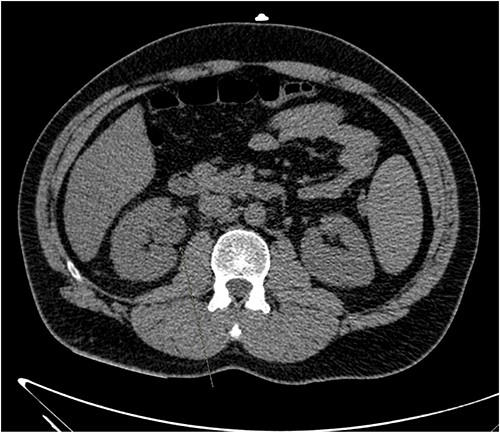

He presented with right sided abdominal pain associated with jaundice, fever, myalgia and arthralgia after receiving his second dose of the penultimate cycle of intra-renal BCG instillation. He did not have any tuberculosis contacts. His parameters on admission were stable. C-reactive protein levels were 230 mg/l and white cell count (WCC) was 6.51 × 109/l. His liver function tests were deranged, with a mixed obstructive and hepatitic picture. A CT kidneys, ureters and bladder (KUB) showed mild diffuse dilatation of the right ureter and renal pelvis with minimal amount of peri-ureteric fat stranding (Fig. 1). A CT scan of the abdomen with intravenous contrast (IV) was performed, this showed a distended right ureter down to the vesicoureteric junction, peri-ureteric fat stranding and lymphadenopathy in the aorto-caval space together with splenomegaly and atelectatic changes (Fig. 2).

A CT scan of the abdomen with IV contrast showed atelactic changes in the lung bases (top left), reactive hilar nodes (top right), a distended right ureter all the way down to the vesicoureteric junction surrounded by fat stranding (bottom left) and splenomegaly (bottom right).